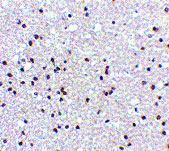

Immunohistochemistry of NPAS3 in human brain tissue with NPAS3 antibody at 5 μg/mL.